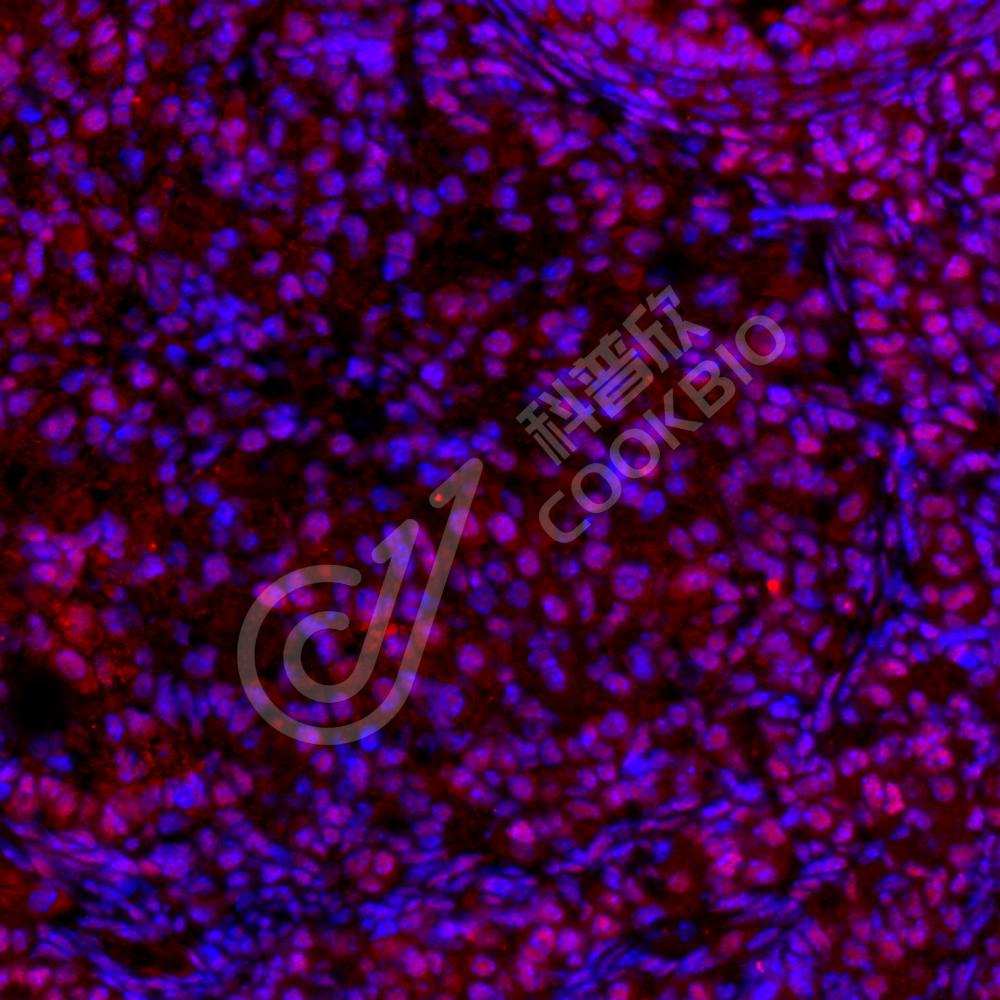

IF检测Estrogen Receptor beta蛋白(货号 K133804)(红色).

样品: 小鼠卵巢, 4%多聚甲醛 (货号KSG1101) 固定12-24小时.

抗原修复: Tris-EDTA抗原修复液(pH 9.0) (KSG1203), 98℃, 20分钟.

封闭: 3% BSA(货号KSGC305010)的PBS溶液, 室温孵育30分钟.

—抗: 1: 600稀释, 4℃ 孵育过夜.

二抗: Cy3标记山羊抗兔IgG (H+L) (货号KB63909), 1: 300稀释, 室温孵育1小时.